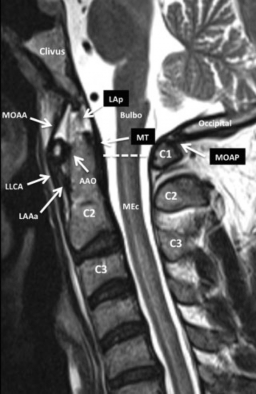

Algunos autores señalan la existencia de un grupo de ligamentos accesorios, de menor desarrollo, que si bien son identificables durante disecciones anatómicas, no son visualizados en estudios de RM de alta resolución. Destacaremos los ligamentos más importantes en la fisiología de la región e identificables en los estudios de RM (►Fig. 7, ►Fig. 8, ►Fig. 9 y ►Fig. 10).

Resonancia magnética (RM), secuencia ponderada en FSE T2, plano sagital. Corte sagital de la UCC en línea media para visualizar las estructuras de la UCC y sobre todo los ligamentos, visualizados como estructuras lineales de baja señal ponderadas en T2. La línea punteada indica la transición convencional entre el bulbo raquídeo y la médula espinal. Abreviaciones: AAO, articulación atloido-odontoidea; C1, 1ª vértebra cervical; C2, 2ª vértebra cervical; C3, 3ª vértebra cervical; LLCA, ligamento longitudinal común anterior; LAAa, ligamento atloido-axoideo accesorio; LAp, ligamento apical; LT, ligamento trasverso; MOAA, membrana occipito-atloido-axoidea; MOAP, membrana occipito-atloidea posterior; MEc, médula espinal cervical; MT, membrana tectoria.